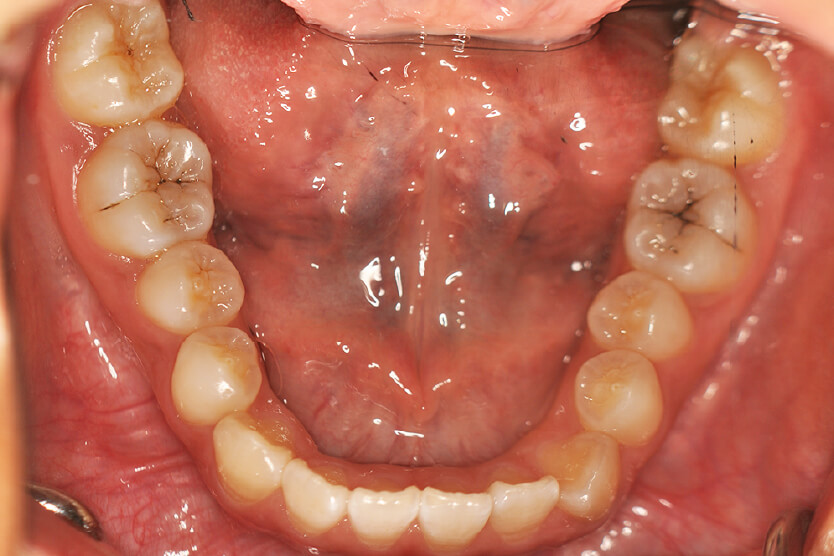

| 治療内容の詳細 | 初診時12歳の女性で、上顎前歯部の反対咬合を気にされ来院されました。 検査の結果、下顎前突、上顎前歯部叢生および上顎側切歯反対咬合を伴うアングルⅢ級不正咬合と診断しました。 治療としては、リンガルアーチを使用して、上顎側切歯を前方へ移動させ、反対咬合の改善を行い、マウスピース型矯正装置(インビザライン)で配列を行いました。 治療期間は1年5か月でした。 |